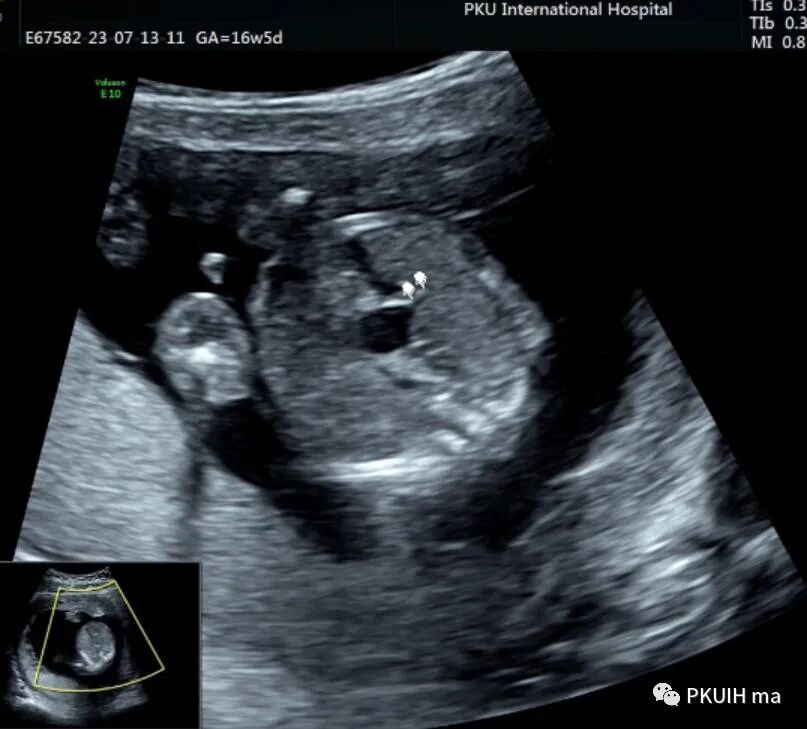

胎儿中腹部见一囊性包块,大小约1.2x1.0x0.8cm,边界清,形态规则,内透声好。囊肿位于脊柱前方、胆囊后方、门静脉窦旁,与后肾接近

观察囊肿与肾、胃泡、膀胱均无相关。

仔细观察囊肿壁好像不完整,周边见微小管道回声与囊肿相通

由于囊肿位于胆囊后方、肝下方、门静脉窦旁,随考虑为胆总管囊肿

本病可于中孕及晚孕期被发现,其超声特征为肝门区囊性包块,形状呈圆形或椭圆形,位于门静脉右前方,可对门脉造成压迫。如果显示囊性包块与胆囊相通,则有助于诊断,彩超一般内部无血流信号。